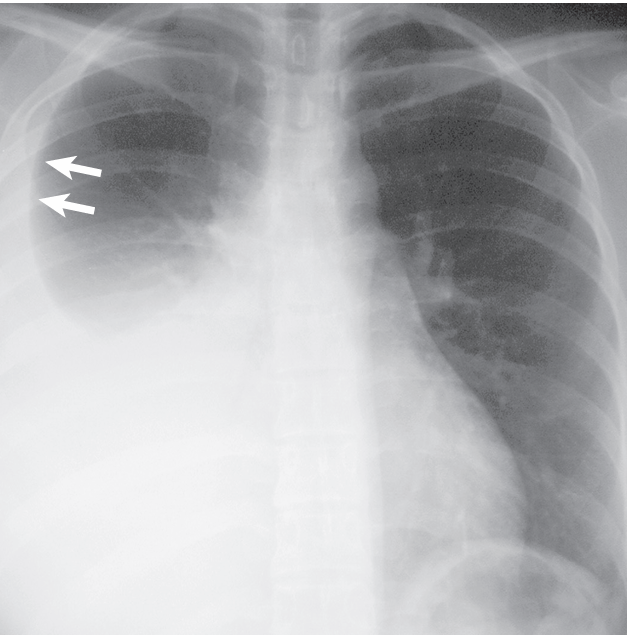

Fig. 72.1 Derrame pleural libre. La radiografía posteroanterior de tórax muestra el signo del menisco (flechas) en un gran derrame pleural derecho.

SIGNOS RADIOGRÁFICOS Signo de menisco en radiografía frontal (>200 mL) Embotamiento del surco costofrénico en vista lateral (>50 mL) Derrame subpulmonar: desplazamiento lateral del ápice del pseudodiafragma SIGNOS DE TOMOGRAFÍA COMPUTARIZADA Opacidad en forma de hoz en la parte más dependiente del tórax, el surco costofrénico posterior en el paciente en decúbito supino Atenuación de líquidos (0–20 unidades de Hounsfield)